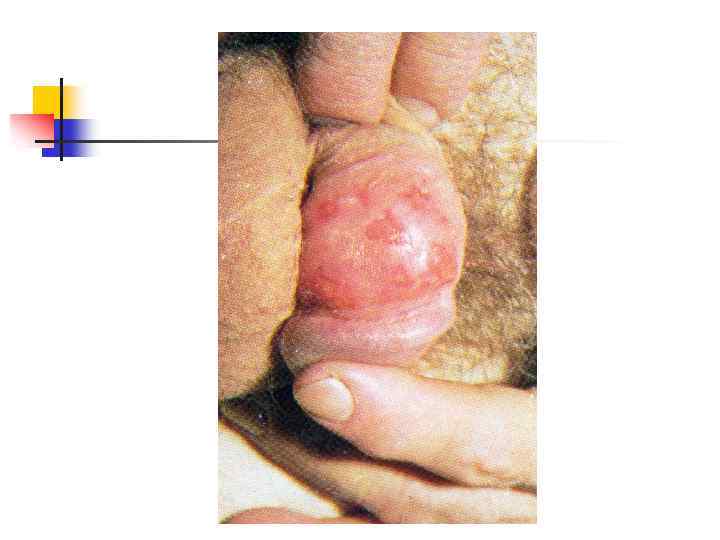

Герпес половых органов: рецидив На теле полового члена группа везикул, сидящих на гиперемированном, слегка возвышающемся основании. В центре некоторых везикул образовались корки

Герпес половых органов: рецидив На теле полового члена группа везикул, сидящих на гиперемированном, слегка возвышающемся основании. В центре некоторых везикул образовались корки